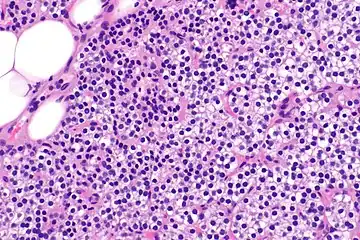

Parathyroid hyperplasia low mag.

Parathyroid hyperplasia medium mag.

Parathyroid hyperplasia high mag.

Primary hyperplasia of the parathyroid gland, results from both hypocalcaemia and increased phosphate levels by decreasing expression of calcium sensing receptors and vitamin D receptors at the parathyroid gland.[8][4] These decreases in receptor expression lead to hyperfunctioning of the parathyroid. Hyperfunction of the parathyroid gland is thought to exacerbate primary hyperplasia which evolves further to a secondary more aggressive hyperplasia. Histologically, these hyperplasic glands can be either diffuse or nodular.[24] Primary hyperplasia, usually resulting in diffuse polyclonal growth is manly related to reversible secondary hyperparathyroidism. Secondary hyperplasia of the parathyroid gland is more often a nodular, monoclonal growth that sustains secondary hyperparathyroidism and is the catalyst in the progression to tertiary hyperparathyroidism. Nodular hyperplastic glands in tertiary hyperparathyroidism are distinctly larger in both absolute size and weight up to 20-40-fold increases have been reported.[25][26][24]

Parathyroid glands are normally composed of chief cells, adipocytes and scattered oxyphil cells.[27][14] Chief cells are thought to be responsible for the production, storage and secretion of parathyroid hormone. These cells appear light and dark with a prominent Golgi body and endoplasmic reticulum. In electron micrographs, secretory vesicles can be seen in and around the Golgi and at the cell membrane. These cells also contain prominent cytoplasmic adipose.[27][14] Upon onset of hyperplasia these cells are described as having a nodular pattern with enlargement of protein synthesis machinery such as the endoplasmic reticulum and Golgi. Increased secretory vesicles are seen and decreased intercellular fat is characteristic.[27][24] Oxyphil cells also appear hyperplasic however, these cells are much less prominent.